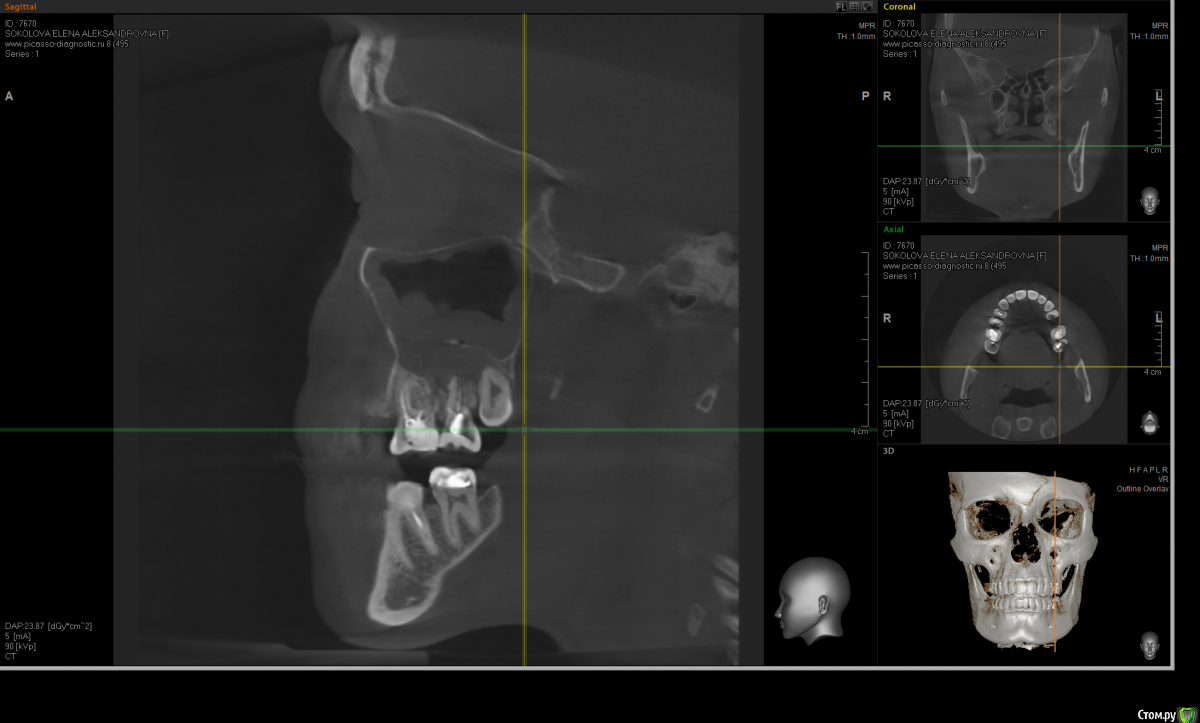

Kostoprav Опубликовано 20 июня, 2015 Поделиться Опубликовано 20 июня, 2015 по данным кт сканам определяеться одонтогенная радикулярная киста в\ч в обл 6,7,8 зубов проросшая в гайморову пазуху + инородное тело (пломбировочный материал ) По моему это работа наша , а не лориков , только санация пазухи не решит проблему Ссылка на комментарий